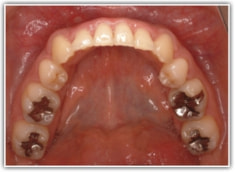

治療後(2年3ヶ月後)

歯根のパラレリング(平行性)が獲得されております。

下顎8番は、両側抜歯済みです。

顎位は良好な状態です。